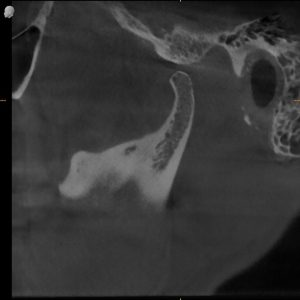

MRI Findings:

- Bilateral disc displacement without reduction

- This explained everything — the pain, the restriction, the dysfunction